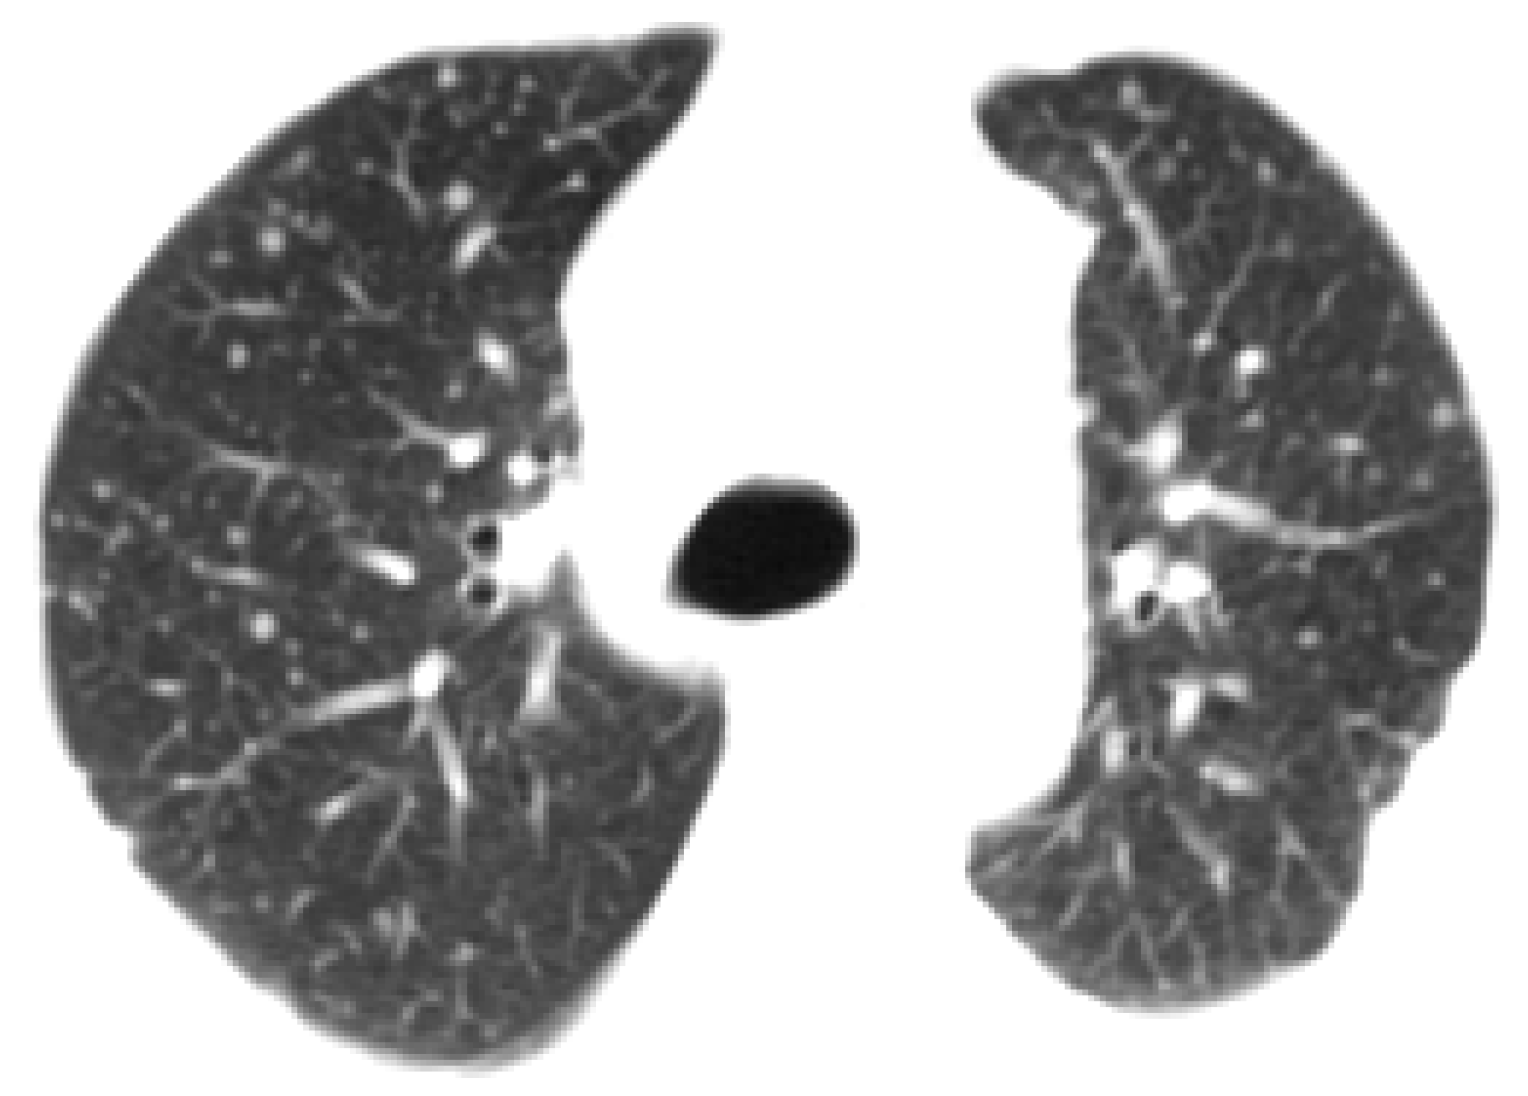

3.3.1. Segmenting the Chest CT Image

3.3.2. Removing Irrelevant Background Areas

3.3.3. Outlining the Lung Areas with a Box Field